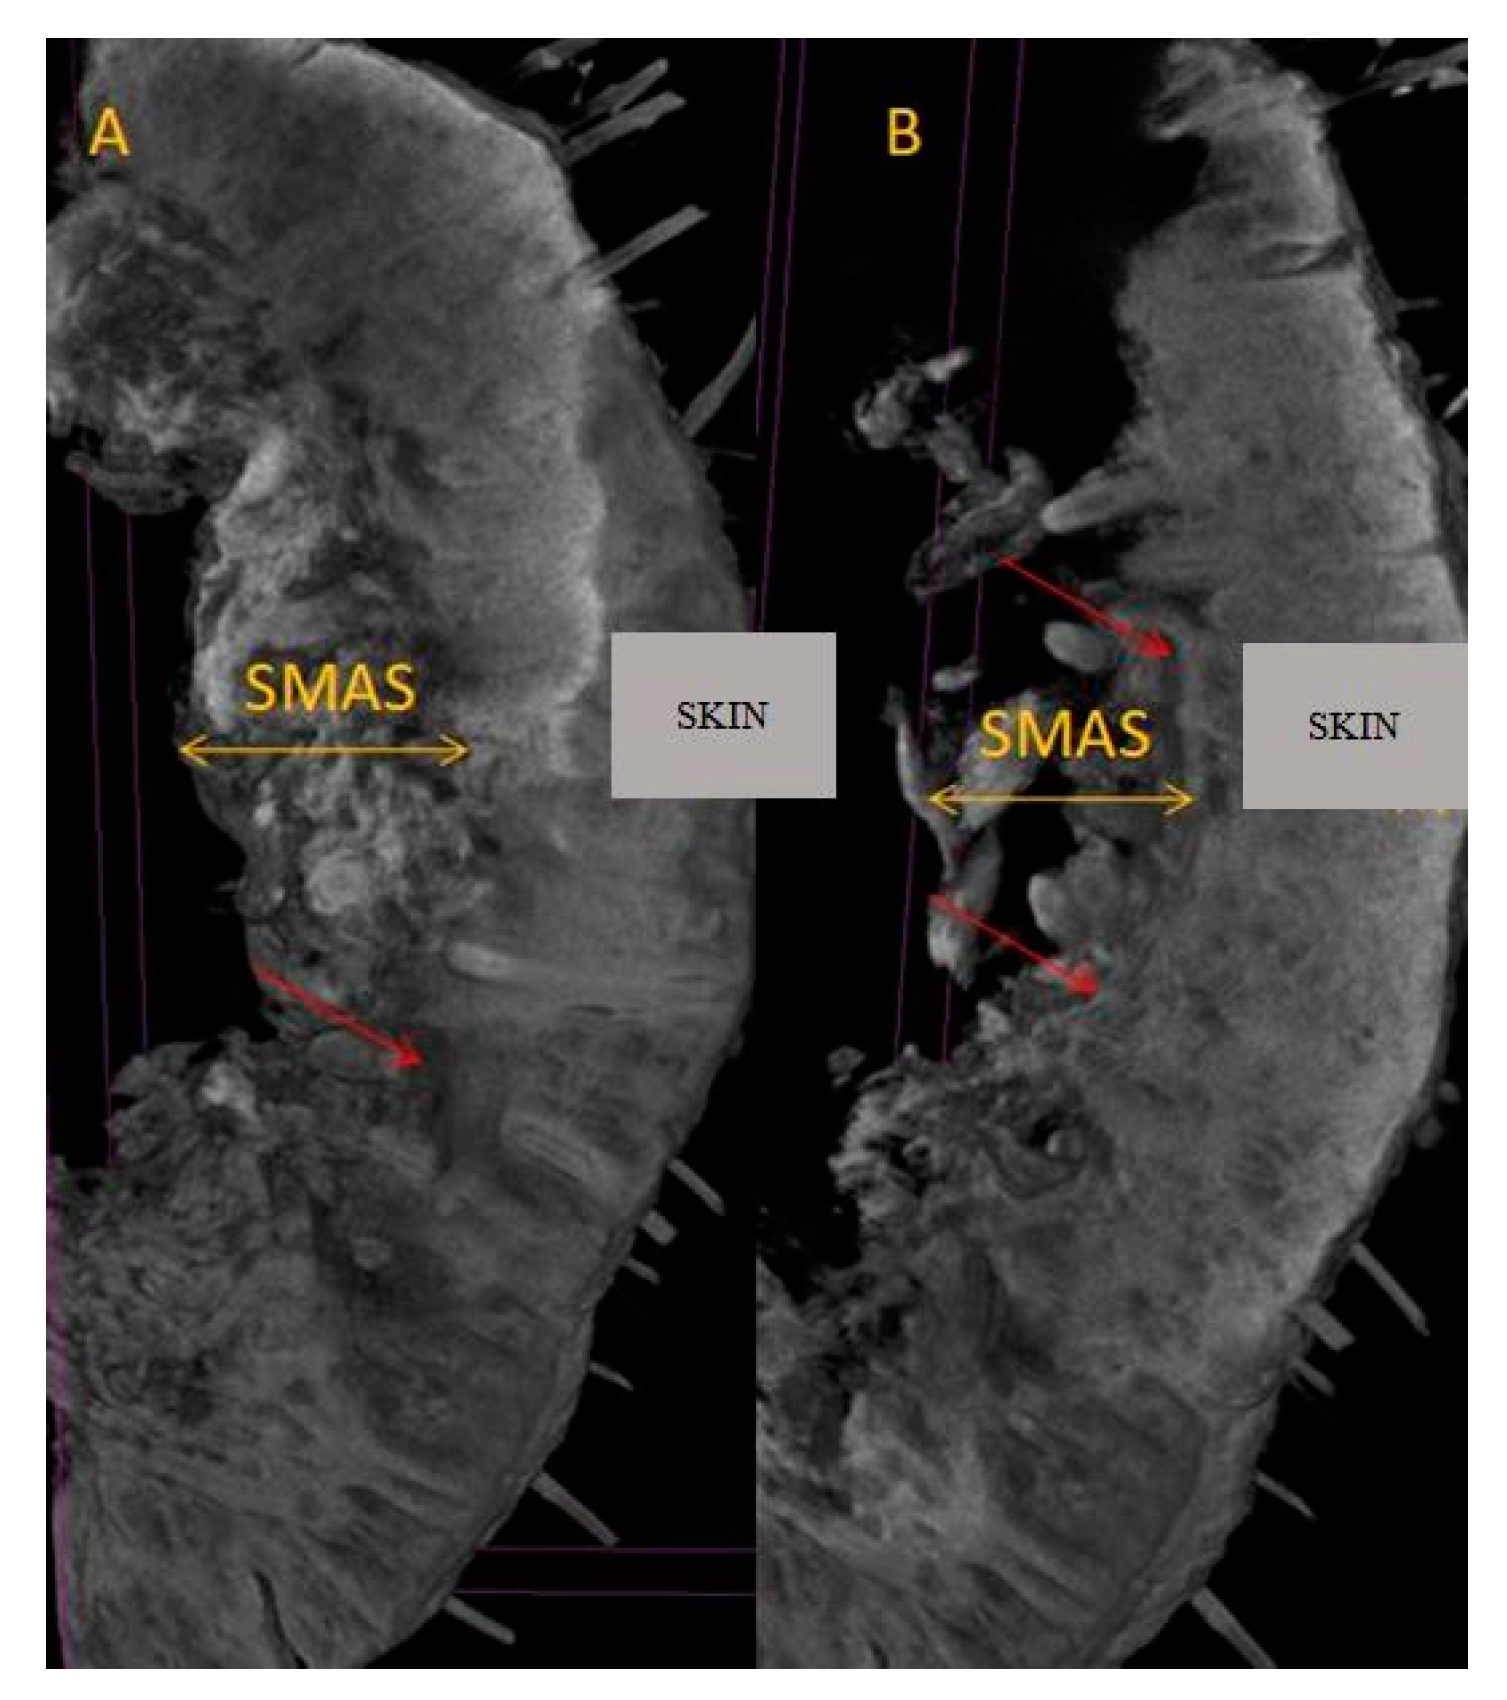

Figure 9. (A) Micro-CT at upper lip level; (B) micro-CT at the level of the lower lip; SMAS blood vessels are highlighted by red arrows.

On the 20 µm scan after 7 days of immersion, we were able to distinguish an entire network of blood vessels within the thickness of the SMAS in the area of the nasal pyramid (Figure 6). They cross the SMAS in a random manner—sagittally, coronary, or tortuously. There are no particular conjunctival tissue fibers that follow the blood vessels in this study. Sagittal vessels split in a “T” shape manner when they reach the skin. Therefore, they form a clearly distinguishable blood distribution system in parallel with the skin.

At the same time, we observed a mixed type of blood vessels in this area; cutaneous thick branches cross the SMAS and deep, thinner branches run within its thickness.

The 20 µm scan showed a better image of the trans-SMAS conjunctival network of tunnels for the passage of cutaneous and proper SMAS blood vessels and nerves. They split as vasculonervous bundles in a T-shaped manner right beneath the skin. Then, these bundles follow the skin in a parallel manner (Figure 8).

After studying the results of the different immersions—7 and 14 days, respectively— we decided that in the case of the oral region, we should leave the pieces in Lugol for two weeks (Figure 9).